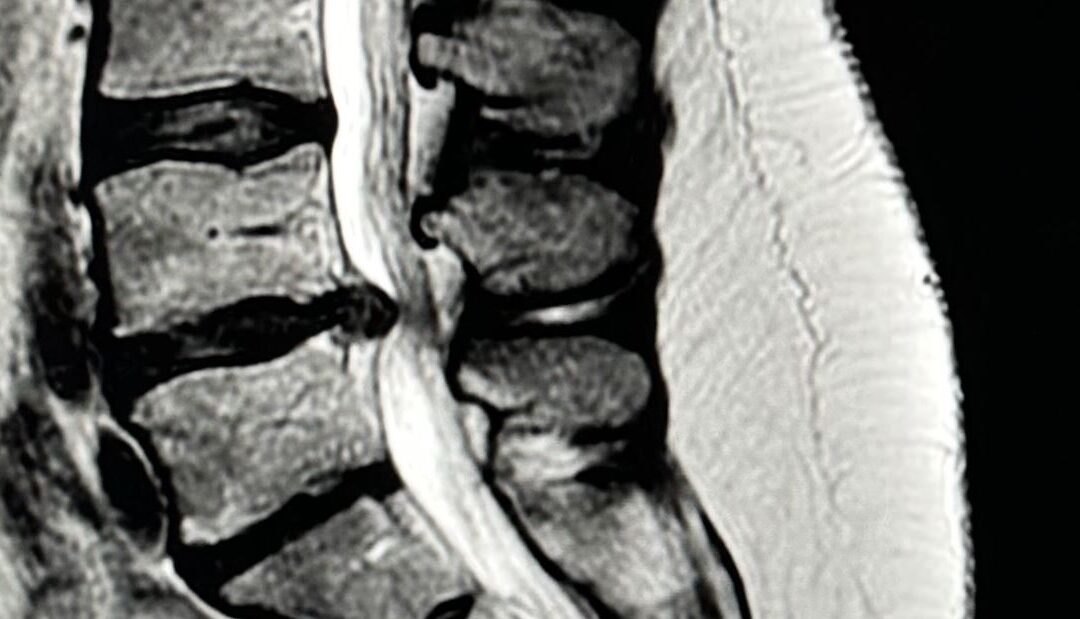

Cuando una hernia discal lumbar provoca dolor en la pierna (ciática), lo primero es intentar un tratamiento conservador: reposo relativo, medicación, fisioterapia o infiltraciones. En la mayoría de casos, estos tratamientos funcionan, pero si el dolor persiste tras...